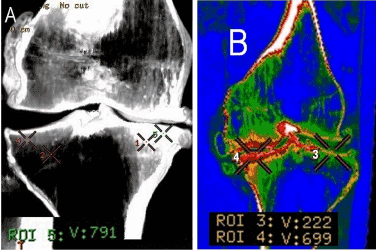

The studies were performed using computer tomographs GE Lihgt Speed VCT (GE Medical Systems, Wisconsin, USA), Toshiba Aquilion-64 (Toshiba Medical Systems corporation, Toshigi 324-8550, Japan). Technical conditions of spiral scanning: software LowerExtremity. Processing of axial slices was done in the mode of multiplanar reconstruction (MPR) in frontal and sagittal planes. The bone density was measured in Hounsfield units (HU). At the third stage we performed analysis of topographic-anatomic changes in mode 3D-reconstruction(VRT) with bone and soft-tissue filters of working stations. The bone density was measured at standard points (Figure 1).

Figure 1. Hip joints MSCT, axial view(A). Knee-joint MSCT, axial view(B), MPR (C). Scheme of bone density measurement in different parts of femoral head, acetabulum, different parts of knee-joint, HU.